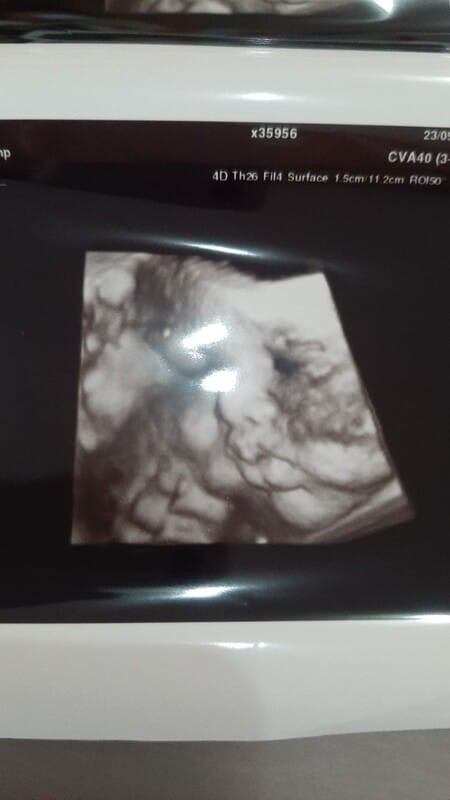

Mau cerita ni bun. Kemarin usg ke dokter usia kandungan 34weeks, dan kepala si dedek masih di atas. Di cek tensi naik 140/90. Keesokan harinya kepuskesmas, karena punya riwayat diabet, sebulan sekali cek lab, dan hasilnya gula naik dari 155 menjadi 201. Langsung dikasih rujukan ke rs, buat konsul dokter kandungan dan dokter dalam. Bidan puskesmas sudah bilang klau gk bisa lahiran di sini, harus di rs . Makin puyeng bun #jangandibully #bantusharing #seriusnanya #mommybuntu